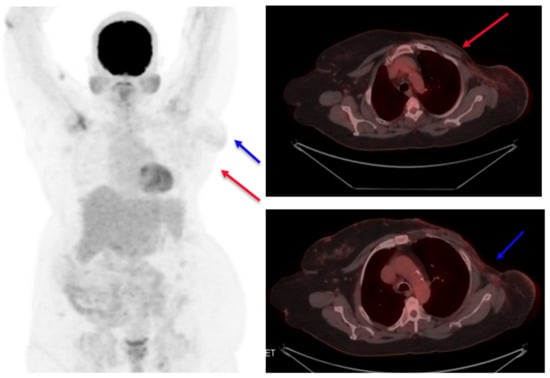

The patient opted for treatment with T-DM1 after thoroughly understanding the clinical situation and a discussion with the healthcare team. As the patient had access to an approved biosimilar option available in our country, the same was selected and given alongside alternate-day hemodialysis. Thus, the neoadjuvant therapy was started with T-DM1, which the patient tolerated well at a dose of 3.6 mg/kg given once every three weeks. A good partial response was observed after six cycles (Figure 3). During the treatment period, her renal disease parameters also had a correction.

Figure 3.

PET scan images at interim assessment after six cycles of T-DM1 (A). Primary tumor (target 1) shown as a red arrow and (B) axillary lymph node (target 2) shown as a blue arrow.